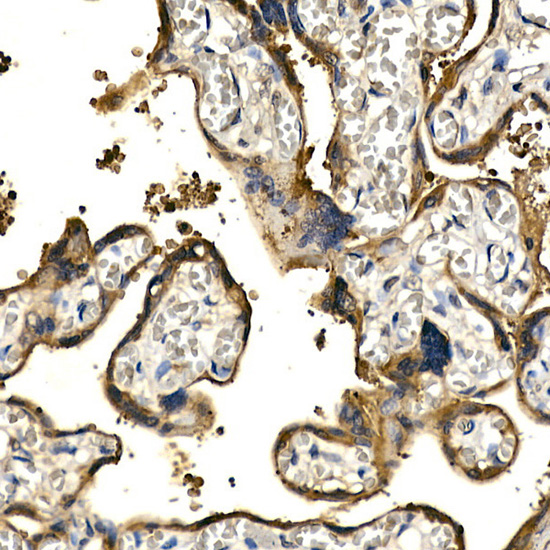

Immunohistochemistry of paraffin-embedded human placenta using PDGFB Rabbit pAb.